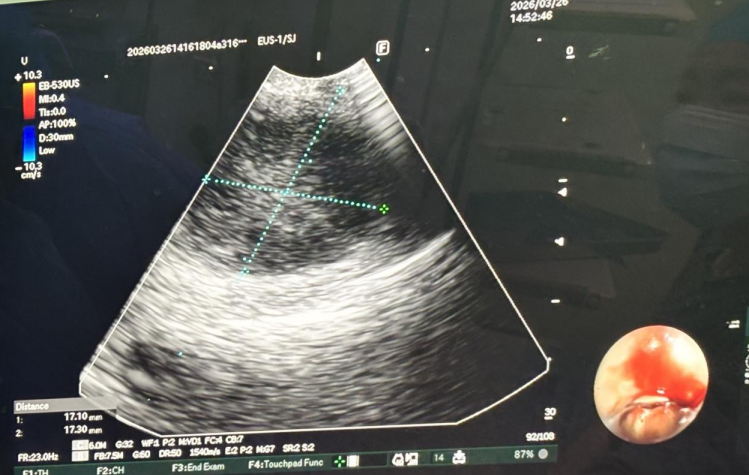

在麻醉科充分的术前准备下,科室为患者实施了EBUS-TBNA术。术中,副主任医师谢波将一根特制的、前端搭载微型超声探头的支气管镜伸入患者气道,通过实时超声扫描,屏幕上清晰地显示出气道外、血管旁的肿大淋巴结位置,完美地突破了传统支气管镜的“视觉盲区”。在超声的精确引导下,将一根细小的穿刺针安全地通过支气管壁,分别于右肺中间段支气管近上叶嵴病灶及4R淋巴结行EBUS-TBNA,成功获取了足量的细胞和组织条送病理及细胞学检查。